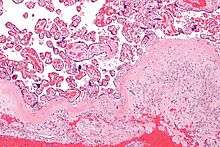

That part of the decidua that interacts with the trophoblast is the decidua basalis (also called decidua placentalis). The remainder of the decidua is termed the decidua parietalis or decidua vera. Also, there is the decidua capsularis, which grows over the embryo on the luminal side, enclosing it into the endometrium and surrounding the embryo together with decidua basalis.

The region of fibrinoid degeneration where trophoblasts meet decidua is called Nitabuch's layer. This layer is absent in placenta accreta.[1]

As the maternal interface to the embryo the decidua participates in the exchanges of nutrition, gas, and waste with the gestation. It also protects the pregnancy from the maternal immune system. Further, the decidua has to allow a very controlled invasion of the trophoblast.

In invasive placental disorders like placenta accreta decidualization have been consistently found to be deficient.